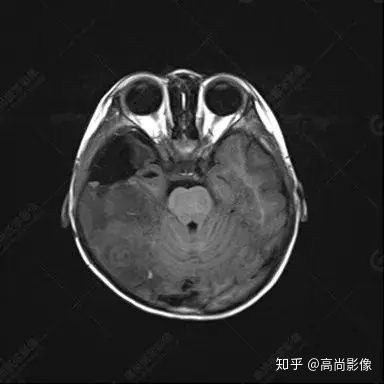

右側(cè)顳葉腫瘤切除術(shù)后(具體不詳):右側(cè)顳部骨質(zhì)不連續(xù)呈術(shù)后改變,右側(cè)顳葉術(shù)區(qū)見片狀長(zhǎng)T1長(zhǎng)T2信號(hào)影,F(xiàn)LAIR呈低信號(hào);術(shù)區(qū)后方右側(cè)顳枕葉見一巨大占位性病變影,邊界欠清,大小約6.2×5.8×4.3cm(前后×左右×上下),信號(hào)不均勻,T1WI呈等稍低信號(hào)間雜少許高信號(hào),T2WI呈高稍低混雜信號(hào),DWI示部分病灶彌散受限,相應(yīng)ADC圖減低,磁敏感序列見部分呈極低信號(hào),增強(qiáng)掃描可見明顯不均勻強(qiáng)化,鄰近硬腦膜及小腦幕增厚并明顯強(qiáng)化;另延髓右前方及右側(cè)橋小腦角區(qū)見一不規(guī)則形異常信號(hào)影,大小約3.2×1.3×3.7cm(左右×前后×上下),呈長(zhǎng)T1稍長(zhǎng)T2信號(hào),F(xiàn)LAIR呈等信號(hào),DWI未見受限,增強(qiáng)后明顯均勻強(qiáng)化,鄰近腦膜明顯強(qiáng)化。鄰近腦實(shí)質(zhì)及右側(cè)顳角明顯受壓;左側(cè)大腦半球未見局灶性信號(hào)異常,中線結(jié)構(gòu)稍左移。

右側(cè)顳葉腫瘤切除術(shù)后:現(xiàn)術(shù)區(qū)后方右側(cè)顳枕葉及延髓右前方占位,右側(cè)顳枕部硬腦膜及小腦幕明顯強(qiáng)化,結(jié)合既往影像資料,考慮為胚胎源性惡性腫瘤,如非典型畸胎樣/橫紋肌樣瘤(AT/RT)或原始神經(jīng)外胚層腫瘤(PNET)。

非典型畸胎樣/橫紋肌樣瘤(AT/RT) 是一種高度惡性中樞神經(jīng)系統(tǒng)腫瘤,臨床罕見,臨床表現(xiàn)無(wú)特異性,好發(fā)于 5 歲以下兒童,尤以 3 歲以下多見,在兒童原發(fā)性中樞神經(jīng)系統(tǒng)(CNS)腫瘤中占 1%~3%。該腫瘤體積一般較大,幕上大于幕下,有明顯的占位效應(yīng)。該腫瘤成分復(fù)雜,囊變、出血、壞死常見。因此 AT/RT信號(hào)混雜,囊性部分呈 T1WI低、T2WI高信號(hào),增強(qiáng)后不強(qiáng)化;若瘤體出血,囊內(nèi)可見T1WI稍高信號(hào)、T2WI低信號(hào),實(shí)性部分在 T1WI上呈混雜等、低信號(hào),在T2WI 及 T2-FLAIR上呈混雜等高信號(hào),增強(qiáng)掃描后大部分呈環(huán)形條帶樣明顯強(qiáng)化,中心壞死區(qū)不強(qiáng)化。另外,該腫瘤實(shí)性成分在DWI上呈高信號(hào),說(shuō)明腫瘤細(xì)胞核密集,水分子擴(kuò)散明顯受限,提示該腫瘤惡性程度高,容易復(fù)發(fā)及轉(zhuǎn)移。